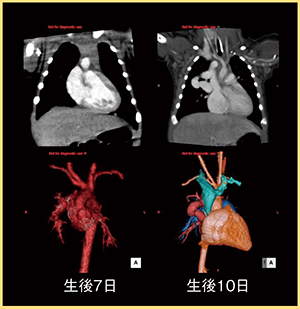

1.小児領域

小児循環器領域において,面検出器CTは圧倒的に有用である。面検出器CTでは上端・下端が等時相の画像を高速に得ることが可能であるため,呼吸停止ができなくとも安定した画像が得られ,鎮静剤が不要となる。特に血管奇形など,上下方向の関係を把握する必要がある検査では非常に有用で,面検出器CTは必要不可欠である(図1)。

図1 小児領域のVolume Scan